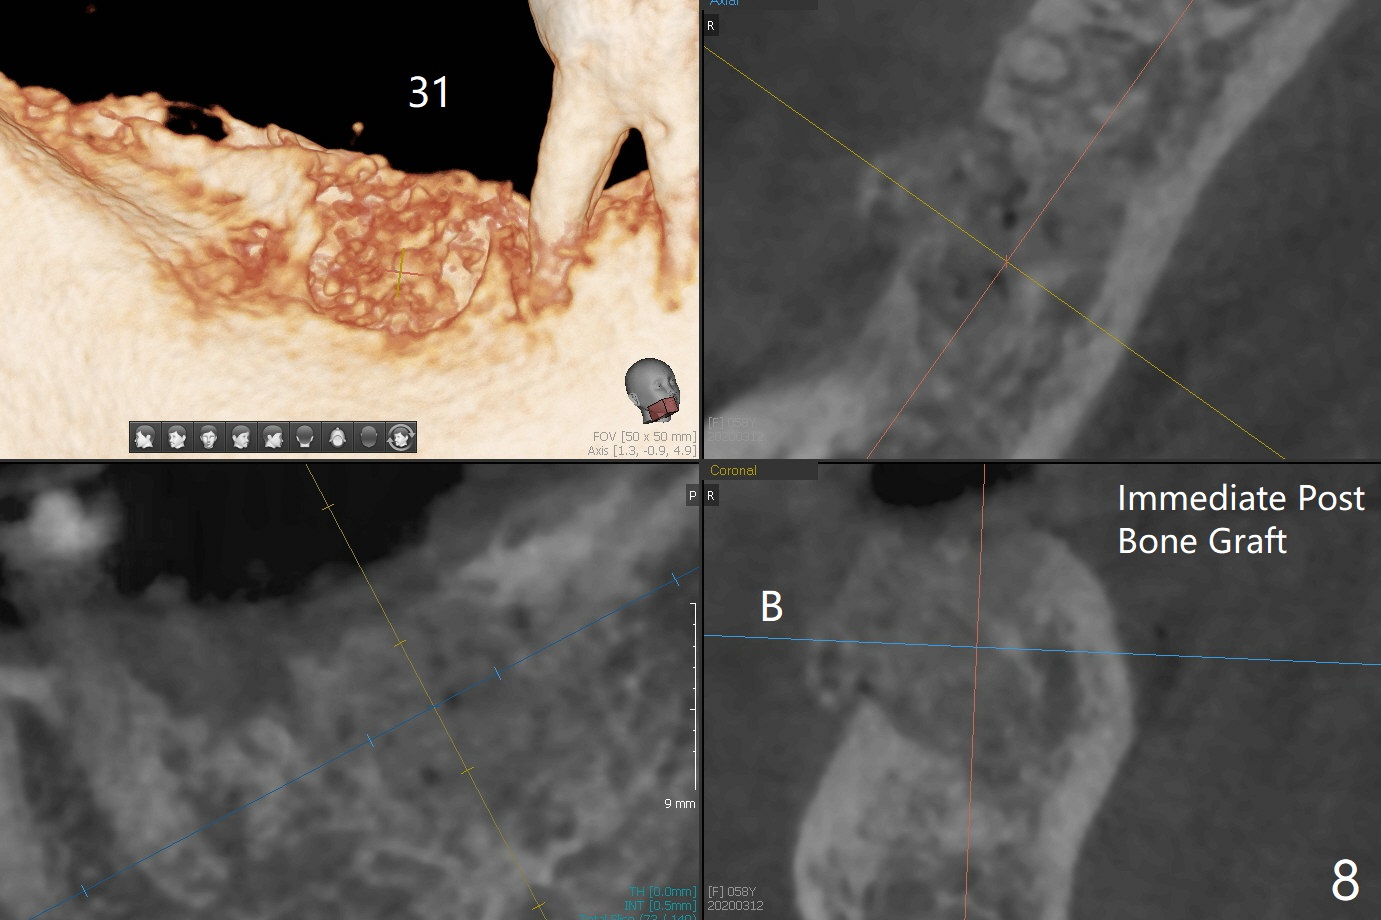

Bone Density Post Extraction with or without Bone Graft

Septum

Critical Area